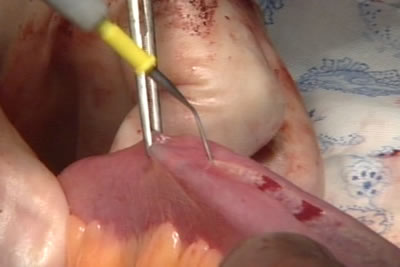

Кишка детубулизируется - рассекается по свободному от брыжейке

краю.

Формируется мочевой резервуар низкого давления из тонкого

кишечника.

Новый мочевой пузырь.